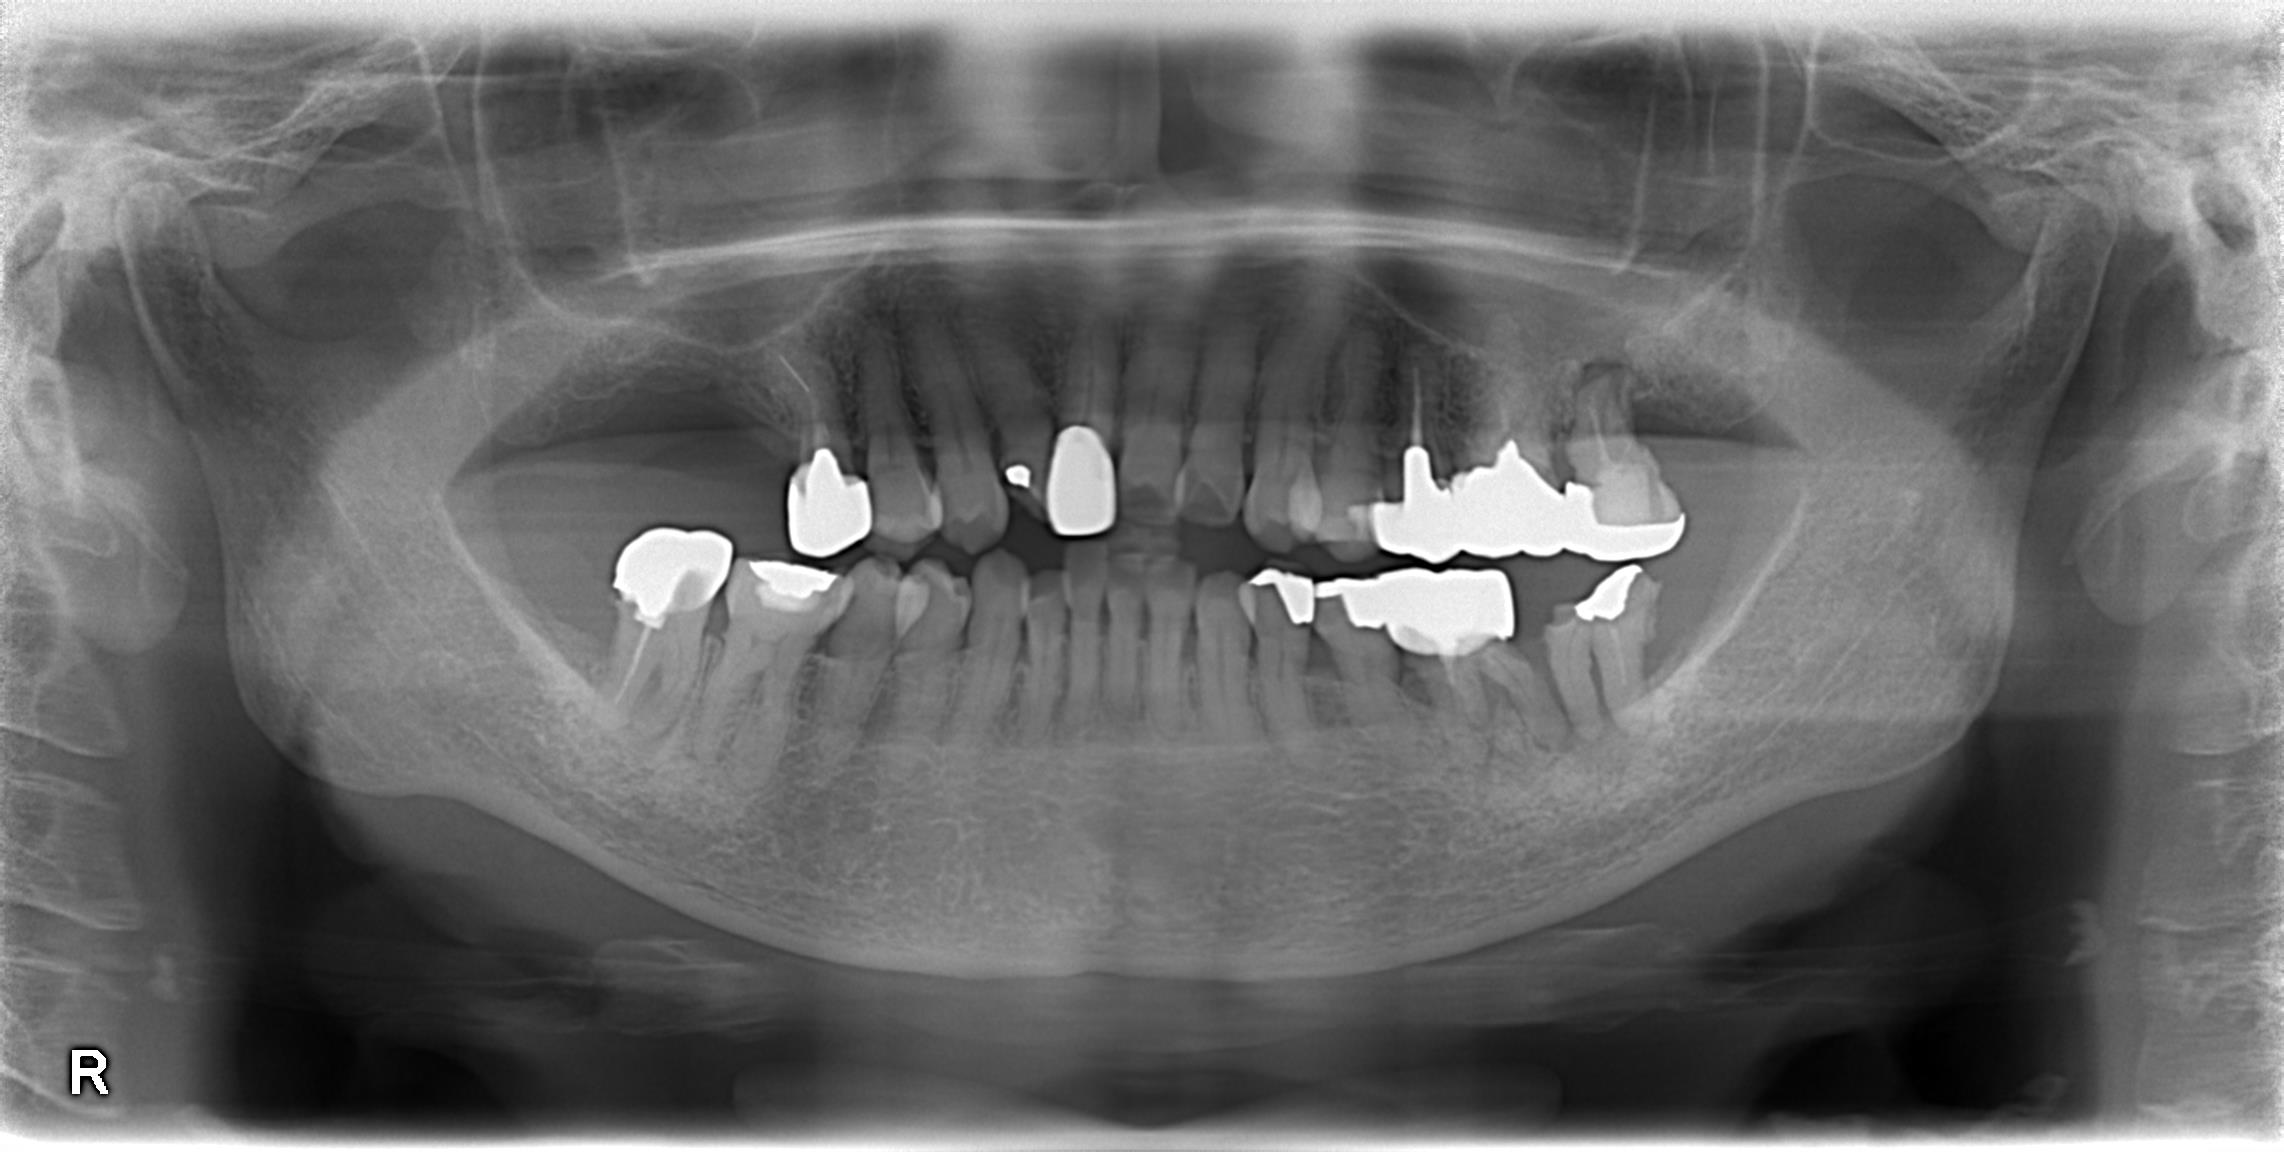

パノラマレントゲン写真です。

右と左が逆に撮影されるので、画像の右が、患者さんの言う左、画像の左が、患者さんの言う右、になります。

60代の患者さんで、

①左下が痛い(画像右下)

②右上にインプラント治療を考えている(画像左上)

という方がいらっしゃいました。前の医院で治療中で、インプラント治療に関してセカンドオピニオンを求めて来院されました。

前医では、「右上のインプラント治療においては、骨が薄く、骨を足すオペをしないといけない、大がかりになる」と言われたそうでした。初めてなのでよくわからず、またその担当の先生のインプラント治療の経験があまりない、とのことから、人づてにささき歯科医院へいらしていただいたという経緯です。